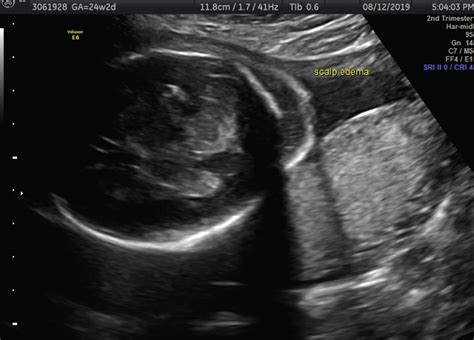

• Swelling: Visible swelling in the fetus, particularly in the extremities, abdomen, or face.

• Abnormal Ultrasound Findings: Ultrasound examinations may reveal fluid accumulation in the fetal tissues or body cavities.

• Ultrasound: Ultrasound examinations are the most common method for detecting fetal edema. They can reveal fluid accumulation in the fetal tissues and body cavities.